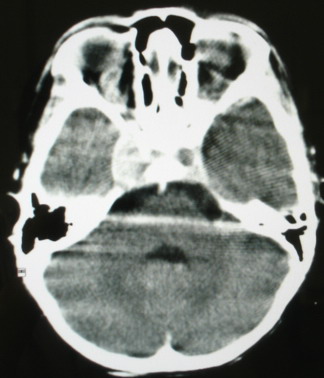

m/8y/,右侧眼睑下垂数日,发育良好,无外伤史,无头痛、恶心、呕吐,学习成绩良好。

ct意见:1、颅内血管畸形。2、右侧海绵窦血管瘤(颈内动脉海绵窦段动脉瘤)。3、脑萎缩。4、建议mr或dsa.

平扫片(骨窗未见异常)

海绵窦瘘.注意眶内静脉有扩张.

右侧海绵窦血管瘤伴右侧海绵窦漏形成(由于右眼上静脉较左侧增粗。故考虑)。

支持 右侧颈内动脉海绵窦瘘.注意眶内静脉有扩张.